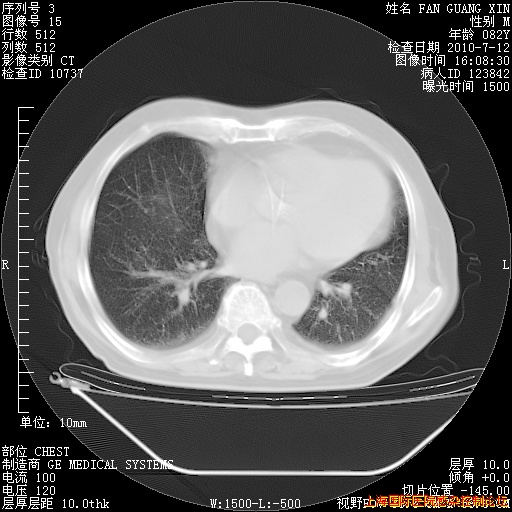

今天复查CT

回复

整整相隔30天的肺部CT好像有所好转啊。甲强龙减量第3天,需要观察体温。

海管,自昨日你和我通完话后,不知您岳父消化道症状有无缓解?体温怎样?阅读7.12日胸部ct,个人认为目前激素治疗是有效的,甲强龙减量是适宜的。因在抗痨治疗,需密切观察肝功、肾功能和血常规。不过,老年、长期住院和大量使用激素,很担心菌群失调发生